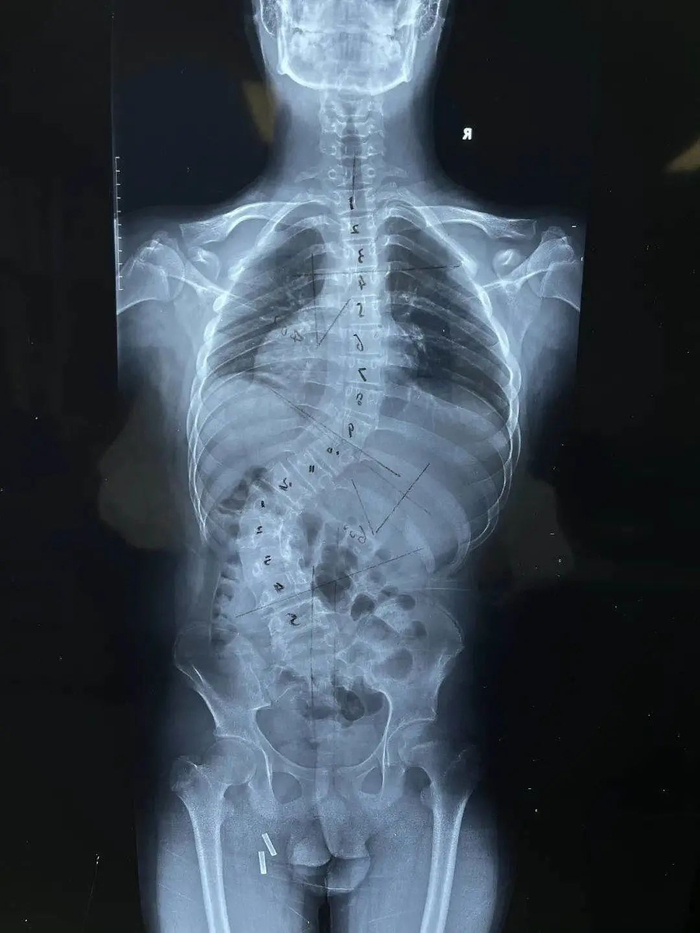

哈尔滨市第五医院脊柱外科医生林佳声接诊后对小宁进行了详细的查体,配合影像科检查诊断为先天性脊柱侧弯、椎管骨性纵隔、脊髓栓系等多种先天性病症,Cobber角60°,进行手术的风险太高。手术需要在小宁腰1椎体的位置进行截骨,然后进行矫形。但手术如果没有达到理想效果,脊髓栓系的症状就会导致小宁出现神经损伤症状。同时,还需要对小宁的椎管骨性纵隔进行切除,复杂的病情加大了手术的风险。稍有不慎,就会出现截瘫。

医生进行了详细的术前情况分析,又与省级龙江名医、哈市五院脊柱外科专家生志刚主任、北京协和医院矫形专家多次对手术方案进行了详细的探讨。在对所有风险都进行一一分析与评估后,于5月4日为小宁进行了“脊柱侧弯截骨矫形术”,手术历经5个小时。术后,患者恢复良好,现在已经可以自行下地行走,而且身高从1.59米增高至1.64米。